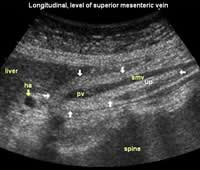

Longitudinal planes from right to left:

![]() Image21 |

![]() Image22 |